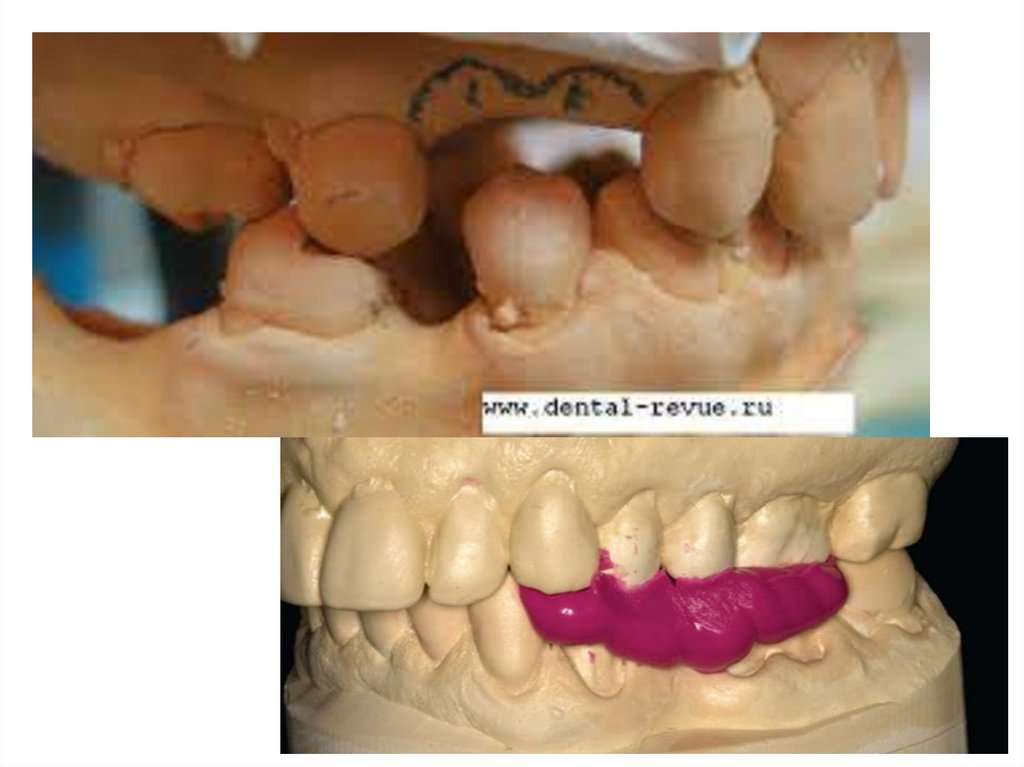

• Смачивают модель, разогревают стандартную восковую

пластинку и обжимают модель, затем по отмеченным

границам базиса обрезают излишки воска.

• Изгибают проволоку и нагрев ее в пламени горелки,

погружают в восковый базис для предупреждения

деформации.

• Изготавливают валик и отрезав часть его по длине,

соответствующей размеру дефекта зубного ряда,

устанавливают его строго по середине гребня и

приклеивают к восковому базису.

• Ширина и высота окклюзионного валика должна быть на 1-2

мм больше рядом стоящих естественных зубов.

• Наружная и внутренняя поверхности окклюзионного валика

должны без резкой границы переходить в поверхность

воскового базиса.